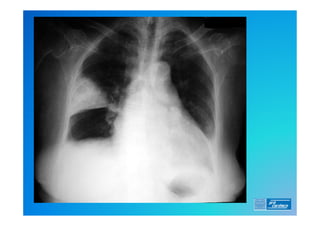

2) RX de Tórax (o que esperar ?)

Diagnóstico . 0) EXAME FÍSICO 1)ECG (alterações frequentes ?) 2) RX de Tórax (o que esperar ?) 3) Laboratório (o que é importante ?) 4) D Dimero 5) Doppler Venoso MMII 6) Ecocardiograma (TT e TE) 7) Angio TC 8) Cintilografia Pulmonar (Ventilação/Perfusão) 9) Angio RM 10) Arteriografia